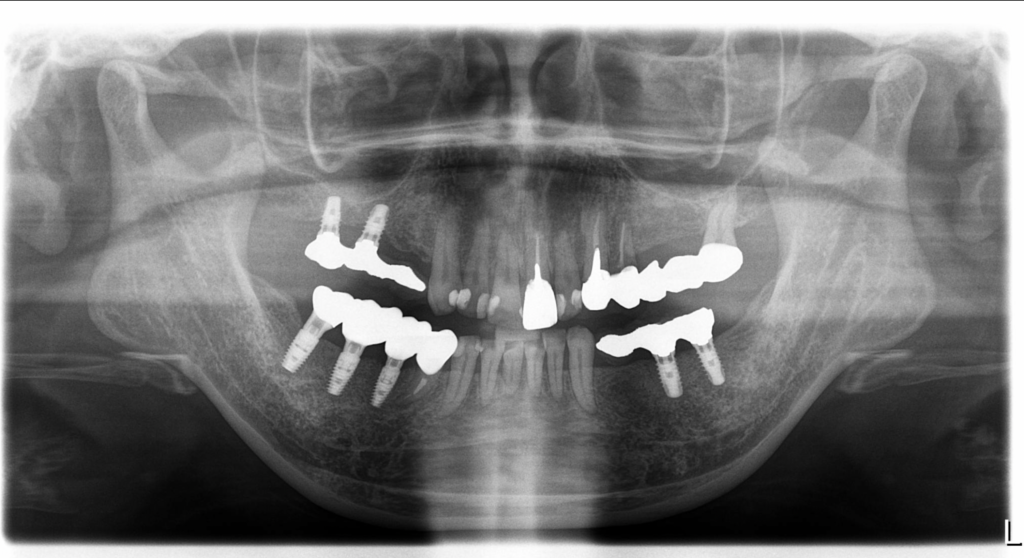

手術後のレントゲン写真です。

サージカルガイドを用いたおかげでシミュレーション通りの位置にインプラントがあります。

矢印のように根が彎曲し近接している場合でも正確な位置に埋入するすることが可能です。